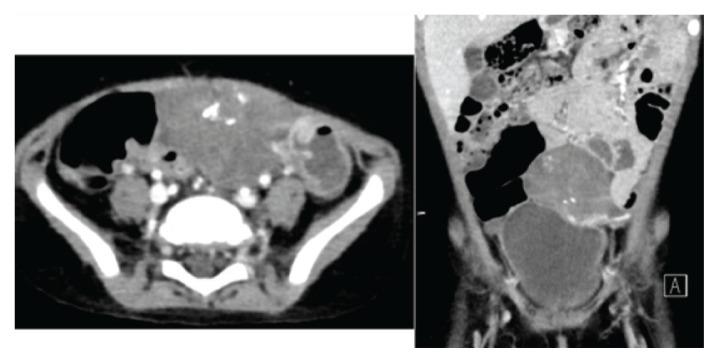

Wilms' tumour (nephroblastoma) is the most common abdominal malignancy in children. Extrarenal Wilms' tumour is rare, with limited reports in the literature. We report a two-year-old girl who presented to a tertiary care hospital in Muscat, Oman, in 2019 with an abdominal mass. The patient was diagnosed with unilateral ovarian Wilms' tumour (initially diagnosed by closed biopsy and confirmed later by histopathology study of the excised tumour). This report highlights the unusual location and presentation of Wilms' tumour and presents the medical challenge in both the initial clinical impression and pathological diagnosis. Furthermore, this report details the therapeutic plan and shows the good outcome achieved by using the classic renal Wilms' tumour therapy protocols.

威尔姆斯瘤(肾母细胞瘤)是儿童最常见的腹部恶性肿瘤。肾外威尔姆斯瘤罕见,文献报道有限。我们报告了一名 2019 年在阿曼马斯喀特一家三级保健医院就诊的两岁女孩,其腹部有一个肿块。该患者被诊断为单侧卵巢威尔姆斯瘤(最初通过闭合活检诊断,后来通过切除肿瘤的组织病理学研究证实)。本报告重点介绍了威尔姆斯瘤的不常见位置和表现,并介绍了在初始临床印象和病理诊断中都存在的医学挑战。此外,本报告详细介绍了治疗计划,并展示了使用经典肾母细胞瘤治疗方案所取得的良好结果。